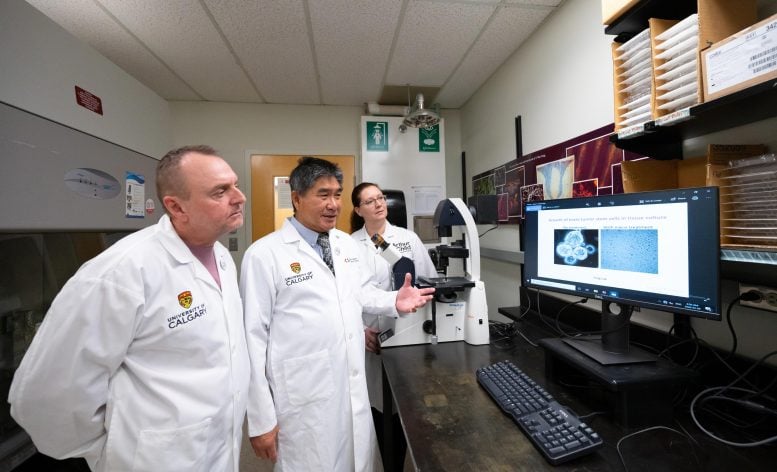

I ricercatori dell’Università di Calgary stanno studiando se dosi elevate di vitamina B3, nota anche come niacina, possano migliorare i risultati se aggiunte al trattamento convenzionale. Waldner è stato invitato a partecipare alla sperimentazione clinica.

Lo studio è condotto dalla Dr.ssa Gloria Roldan Urgoiti, oncologa specializzata in tumori cerebrali e dal Dottor Wee Yong, neuroscienziato che studia le risposte immunitarie nel cervello. Entrambi sono affiliati all’Hotchkiss Brain Institute e all’Arnie Charbonneau Cancer Institute. Il loro obiettivo è determinare se la niacina possa ripristinare la funzione delle cellule immunitarie indebolite, in modo che possano attaccare più efficacemente le cellule tumorali.

La ricerca è iniziata con esperimenti di laboratorio sui topi, nei quali è stato dimostrato che la niacina prolunga la sopravvivenza. Questi risultati hanno gettato le basi per una sperimentazione clinica di fase I e II sui pazienti.